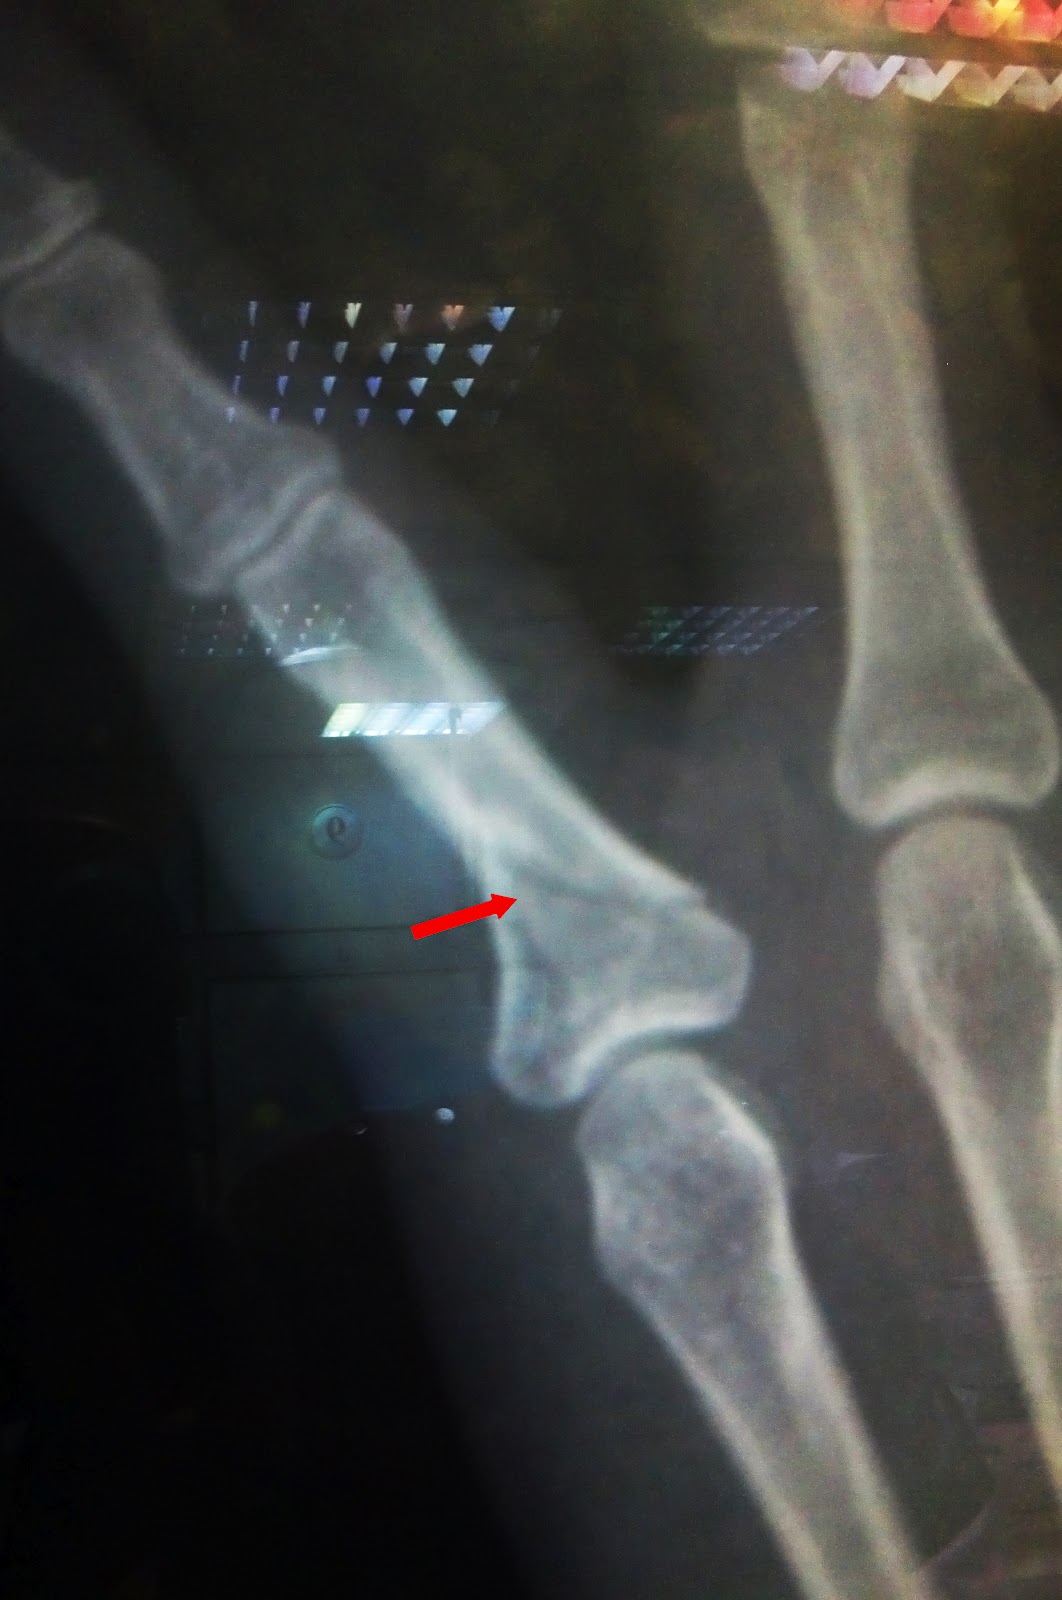

Finally he gave me his opinion. It is not healed. He showed me the

x-ray. Ok. Now what? Three more weeks of this splint?

doctor (HOD). Fantastic! He took me to see my x-rays. It was almost fracture

the whole way through. That explains the bend to the side. HOD and the other